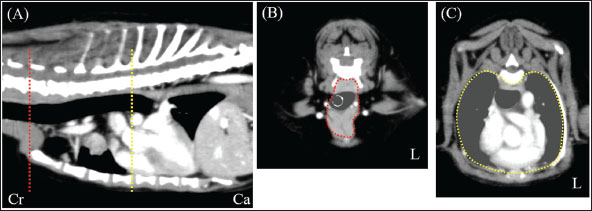

A neutered 9-year-old male Papillon weighing 3.5 kg was referred to the Okayama University of Science Veterinary Medical Teaching Hospital for examination and treatment of an incidentally discovered mass in the cranial intrathoracic cavity during regular medical checkups. The dog had no clinical signs and was in good general condition. However, a mass in the cranial thoracic region was detected by chest radiography. Blood tests showed no hypercalcemia, and arterial blood gas analysis showed no problems (Table 1). Polycythemia, slight hypernatremia, and hyperchloremia, which may be related to dehydration, were also observed. A chest X-ray revealed a mass of approximately 20 mm in the cranial intrathoracic cavity and mild expansion of the mediastinum (Fig. 1). The tumor-associated syndromes, such as megaesophagus and myasthenia gravis, were not observed. Computed tomography (CT) was performed under general anesthesia (Aquilion Lightning; Canon Medical Systems Co., Tokyo, Japan). Iopamidol (Oypalomin 300, Fuji Pharma, Japan) was used as a contrast medium (injection volume, 2.5 ml/kg [750 mgI/kg]; injection time, 15 seconds). Precontrast, arterial phase, venous phase, and equilibrium phase scans were obtained. The cranial intrathoracic mass (length, width, and height of 18.3, 16.0, and 18.6 mm, respectively) was a solitary lesion within the cranial mediastinum (Fig. 2). The mass was well demarcated, and there was no evidence of invasion into the surrounding blood vessels. The CT values of the mass were 43.2, 50.6, 113.1, and 102.2 HU for the precontrast, arterial, venous, and equilibrium phases, respectively (Fig. 2). These contrast enhancement effects were a preliminary diagnosis that the mass was a thymoma (Von Stade et al., 2019). Enlarged surrounding lymph nodes or distant metastasis were not detected. Due to the small size of the mass and its absence from the thoracic cavity margin, preoperative pathological examination could not be performed. Based on the CT results, the mass was provisionally diagnosed as a thymoma. The thymoma volume was measured from the length, width, and height by computed tomography using the elliptical volume formula. The cranial intrathoracic volume was measured using a 3D image analysis software (Ahmics-VAZE, PetCommunications Co., Ltd., Osaka, Japan). The cranial intrathoracic region between the first and fourth sternum at the beginning of the cranial intrathoracic cavity was assumed to be the surgical space for VATS-T (Fig. 3). The dorsal cephalic end was designated as the point where the first sternum extends perpendicularly and joins the thoracic vertebrae, and the dorsal caudal end was designated as the point where the fourth sternum extends perpendicularly and joins the thoracic vertebrae. This region was extracted and its volume was measured using the 3D volume rendering function by Ahmics-VAZE. The ratio of thymoma volume to cranial intrathoracic volume (T/CI ratio) was calculated as follows: thymoma volume/cranial intrathoracic volume × 100). The thymoma volume was 2.3 cm3, the cranial intrathoracic volume was 97.7 cm3, and the T/CI ratio was 2.4%. The thymoma volume was calculated using the approach in a previous report of two cases that described the thoracoscopic resection of thymomas (Mayhew and Friedberg, 2008). We also calculated the cranial intrathoracic volume for the dog, as it was of the same breed and weight as the two reported cases. Subsequently, we calculated the T/CI ratio. In previous reports, the thymoma volumes were 9.5 cm3 and 36.6 cm3, respectively, and the cranial intrathoracic volume was 892.8 cm3. The T/CI ratios were 1.1% and 4.1%, respectively.

Fig. 3. CT imaging of the cranial intrathoracic cavity. (A) Sagittal section. (B) Transverse section of the first sternum. (C) Transverse section of the fourth sternum. The surgical space for VATS was assumed to be the cranial intrathoracic cavity between the first and fourth sternum (A; red and yellow dotted line, respectively). Cross-sections (B and C) of the two dotted lines. The circular areas enclosed by dotted lines within the cross-sections were continuously extracted and designated as the intracranial thoracic cavity, and their volumes were measured. (L): Left side, (Cr): Cranial, (Ca): Caudal.

In recent years, VATS-T has been performed in veterinary medicine (Mayhew and Friedberg, 2008; Alwen et al., 2015; MacIver et al., 2017; Carroll et al., 2024). However, the criteria for its application have not yet been established. Two previous reports evaluated the indications for VATS-T. The first report established the following criteria: dogs weighing >20 kg, non-invasive tumors with a tumor volume of less than 300 cm³, and a tumor diameter of 8 cm (MacIver et al., 2017). The first criteria are only applicable to large-breed dogs and cannot be applied to small-breed dogs, such as those in our case. In large breed dogs, relatively small thymomas may allow sufficient thoracic cavity space for VATS-T (Mayhew and Friedberg, 2008; Alwen et al., 2015; MacIver et al., 2017; Carroll et al., 2024). However, small thymomas may not have sufficient space in the cranial intrathoracic cavity in small-breed dogs. Another report established the criterion of tumors with a maximum diameter-to-body weight ratio of approximately 0.02 (Carroll et al., 2024). The second criterion is based solely on the maximum tumor diameter and does not account for the 3D tumor volume. Additionally, the chest shape can vary significantly depending on the breed, even in dogs of the same weight. Therefore, body weight-based evaluation may not be appropriate. The feasibility of VATS-T in small-breed dogs ultimately depends on the judgment of the surgeon. In this study, the T/CI ratio obtained from CT data may provide an objective means of evaluating the relationship between thymomas and the CI in individual cases. Thymoma resection via VATS-T is feasible in small breeds of dogs. The T/CI ratio for this case (2.4%) was similar to those for previous VATS-T cases (1.1% and 4.1%, respectively). VATS-T may be feasible for cases with a T/CI ratio of approximately 5% or less.

Cranial intrathoracic cavity opened during thymectomy has no specific definition. In this study, we defined the cranial intrathoracic region using the T/CI ratio to represent the area from the tip of the first sternum to the caudal end of the fourth sternum. The tip of the first sternum is located in the cervicothoracic part and is not included in the surgical space. The actual intrathoracic cavity begins around the first sternum’s center. However, the region designated as “around the center” of the first sternum may be ambiguous when measuring the cranial intrathoracic volume. Therefore, the tip of the first sternum was designated as the cranial end. The caudal end of the fourth sternum was assumed to be the most caudal point where the actual VATS space could be used.